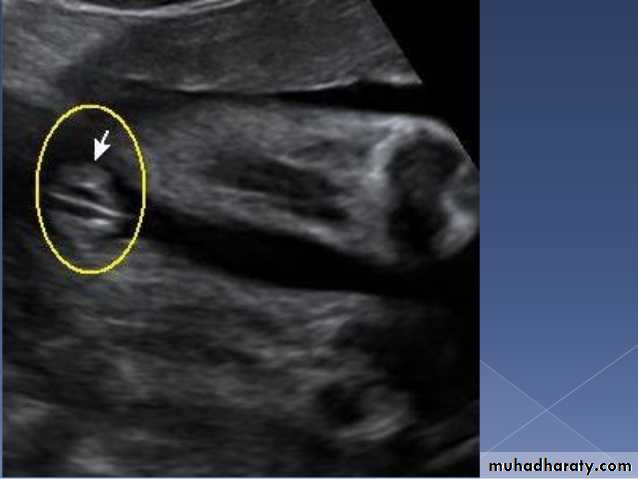

Male or female